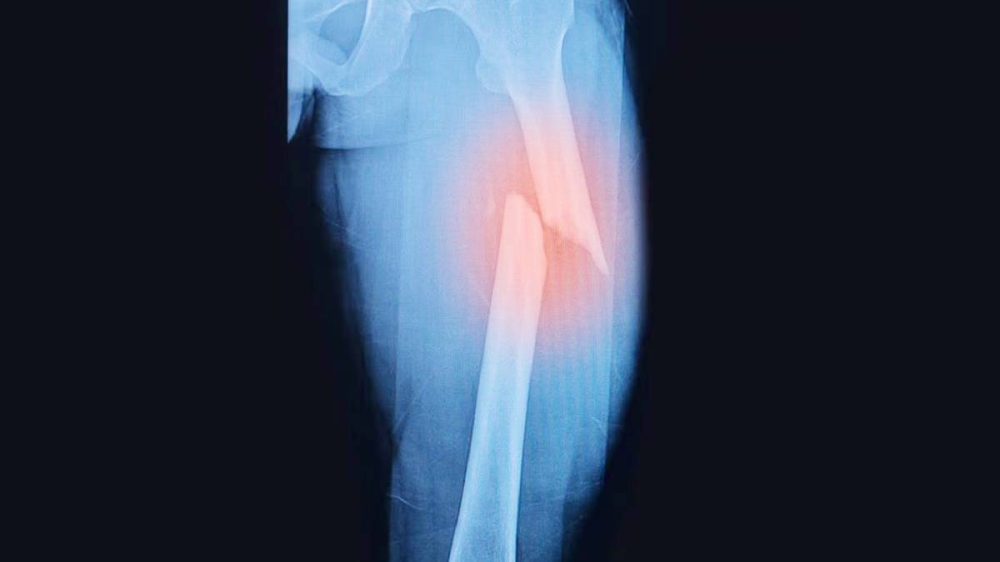

كشف علماء يابانيون عن تقنية جديدة لشفاء العظام المكسورة، تعزز قوة العظام بأكثر من ثلاثة أضعاف بجانب تسريع عملية التعافي. يتم استخدام تقنية تشعيع البلازما في هذا النهج المبتكر الذي يعد واعدًا في مجال علاج الكسور المعقدة. أظهر الباحثون في جامعة أوساكا ميتروبوليتان نجاح الطريقة من خلال التجارب على فئران المختبر.

تظهر التجارب الناجحة على الفئران المختبرة فعالية تقنية تشعيع البلازما في تعزيز قوة العظام وتسريع عملية شفاء الكسور. يعتقد العلماء أن هذه التقنية يمكن أن تحدث ثورة في علاج الكسور المعقدة وتقديم حلاً جديدًا وفعالًا للمرضى. وتعد هذه الابتكارات الطبية الهامة خطوة نحو تحسين جودة الرعاية الصحية وتقديم علاجات مبتكرة للأمراض والإصابات.

تعد تقنية تشعيع البلازما واعدة في مجال علاج الكسور وتعزيز قوة العظام، حيث يمكنها تحسين جودة حياة المرضى وتقليل مدة العلاج. تعمل هذه التقنية على تحفيز نمو العظام وزيادة كثافتها، مما يساعد في شفاء الكسور بشكل أسرع وتقوية العظام بشكل كبير.